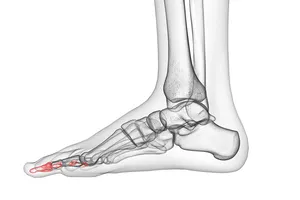

2. 망치발가락

발가락의 중간 마디가 위로 굽어져 망치처럼 보이는 변형으로, 발가락에 통증을 유발하는 흔한 질환입니다. 주로 두 번째 발가락에 발생하지만 다른 발가락에도 나타날 수 있습니다. 먼저 발가락에 공간이 충분한 굽이 낮은 편안한 신발로 바꿔 신는 것이 중요합니다. 발가락을 펴주는 스트레칭과 함께 발가락 교정기나 패드를 사용하여 증상 완화를 시도해 볼 수 있습니다. 통증이 심할 경우 소염진통제 복용이나 스테로이드 주사를 고려할 수 있습니다. 하지만 이러한 보존적인 치료에도 불구하고 증상이 호전되지 않거나 변형이 심한 경우에는 수술을 통해 교정해야 할 수 있습니다.